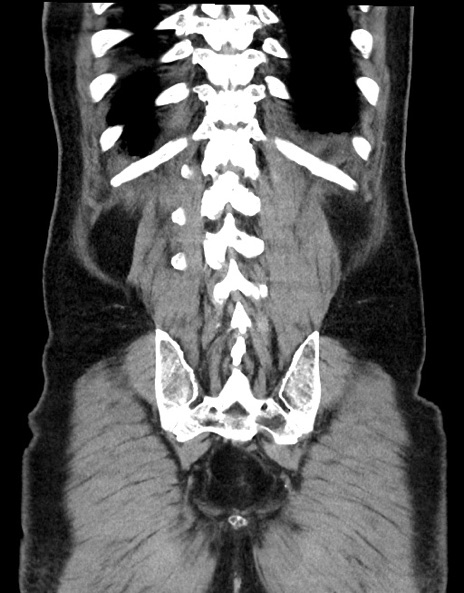

横断像

【症例】70歳代男性

【主訴】腹痛

【現病歴】今朝から腹痛あり。全体的に痛い。特に左上の方。排ガスが今日はない。冷や汗が出る。

【既往歴】直腸癌術後

【身体所見】左側腹部〜上腹部に圧痛あり。腹膜刺激症状明らかなではない。軽度反跳痛。左下腹部に術後瘢痕あり。

【データ】WBC 7700、CRP 0.02